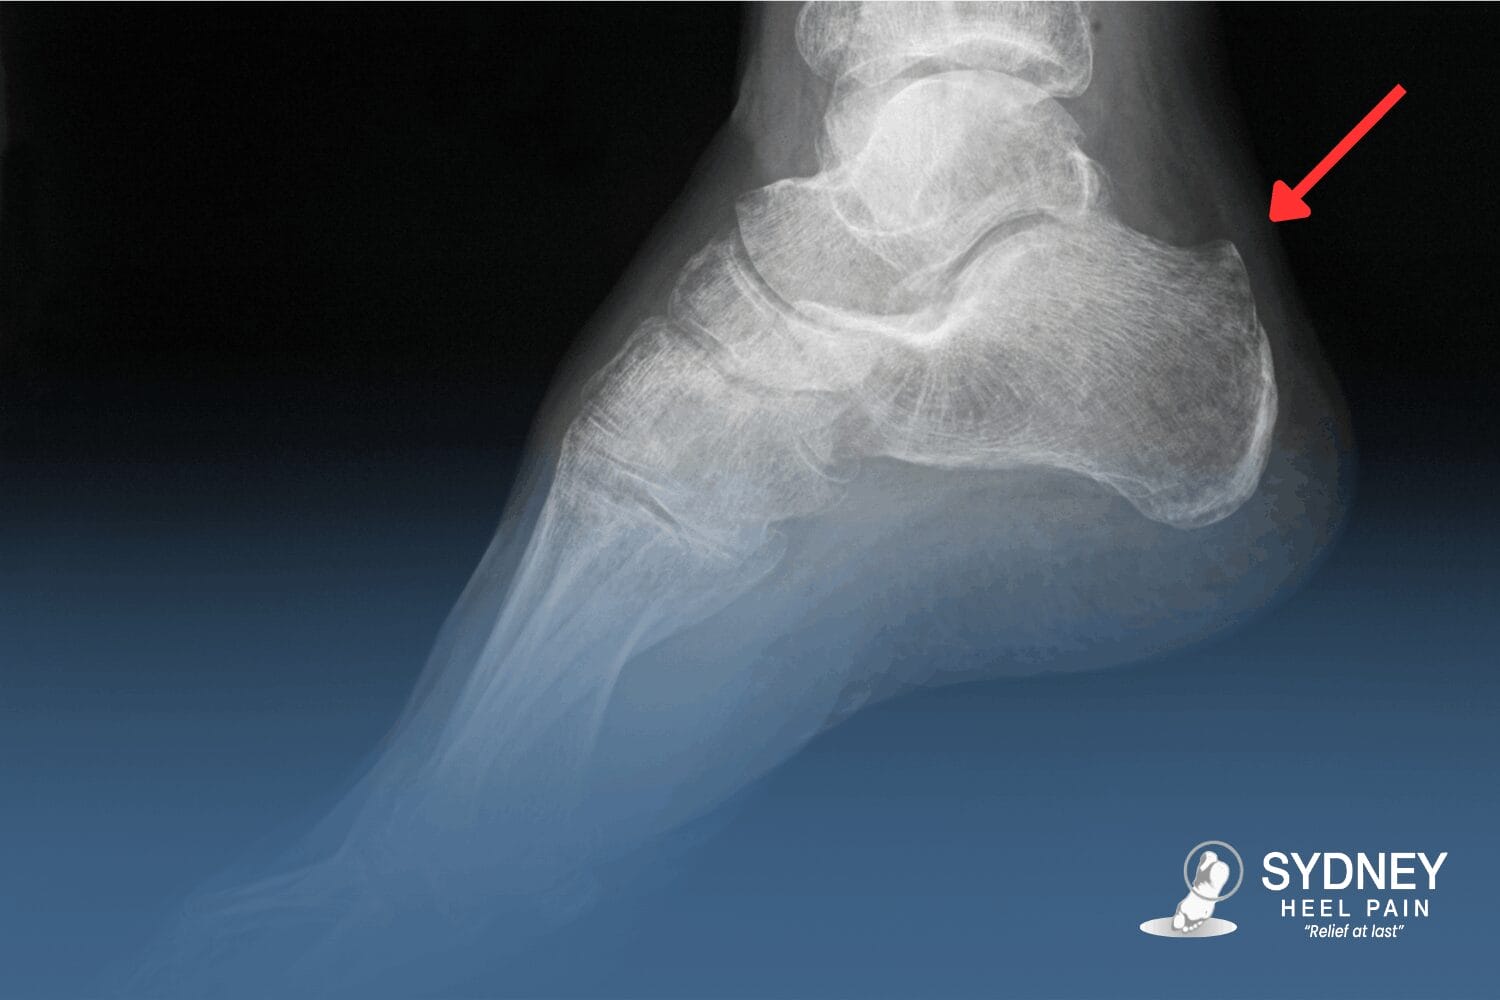

Running, sport, long hours on your feet, and sudden footwear changes often trigger symptoms. Pain is felt at the back of the heel where the Achilles tendon inserts into the heel bone and often intensifies with the first steps after rest or during push-off while walking.